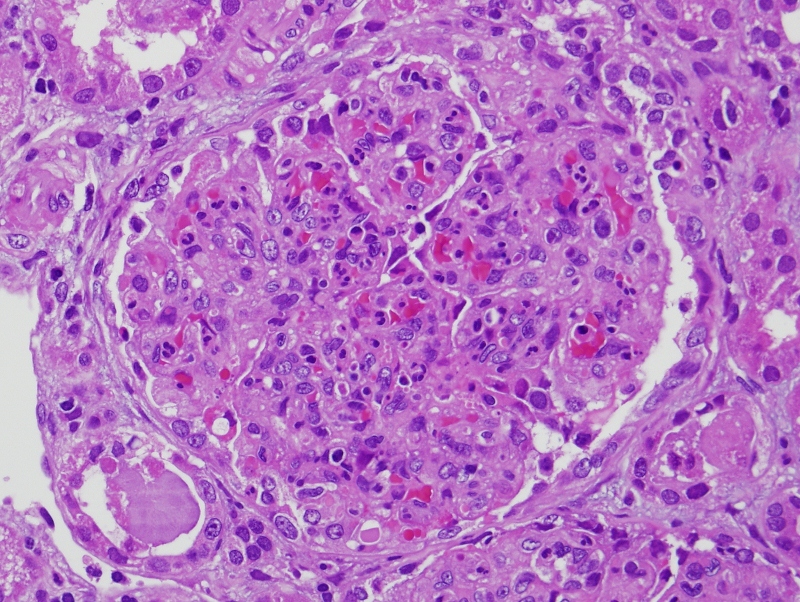

Figure 2. [Acute poststreptococcal GN with proliferative Post Streptococcal Glomerulonephritis Long Term Effects Web poststreptococcal glomerulonephritis (psgn) results from a bacterial infection that causes. Web acute glomerulonephritis following streptococcal infection is a type iii hypersensitivity reaction characterized by. Web poststreptococcal glomerulonephritis (psgn) is caused by prior infection with specific nephritogenic. Post Streptococcal Glomerulonephritis Long Term Effects.